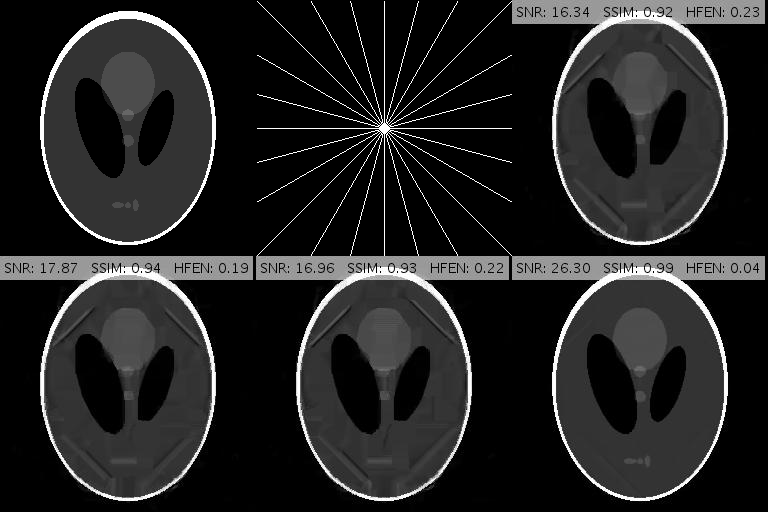

To test the performance of GADMM we choose a Shepp-Logan phantom of size and simulate the k-space data by taking the FFT of the phantom. Then we sample the k-space along 12 radial projections and reconstruct with Algorithm 1 and Algorithm 2. Parameter choices for Algorithm 1 were given in Subsection 3.1. In Algorithm 2 we set , and tune for optimal performance.

Fig. 3 compares reconstruction results for GADMM and Algorithm 1 after 300 iterations of each method. Algorithm 1 outperforms GADMM in SNR by more than 8dB and removes almost all the artifacts that GADMM fails to eliminate. SSIM and HFEN plots for these methods are presented in Fig. 4. The three variants of GADMM run for 121.2 (), 115.1 () and 110.2 () seconds while the Malitsky-Pock method runs for 119.6 seconds. We remark that numerical results of GADMM in this section were only provided to justify our unusual choice of Malitsky-Pock algorithm over ADMM-based methods which are more popular in constrained minimization settings. In the remainder of the paper we solely focus on Algorithm 1 and discard GADMM from further consideration.